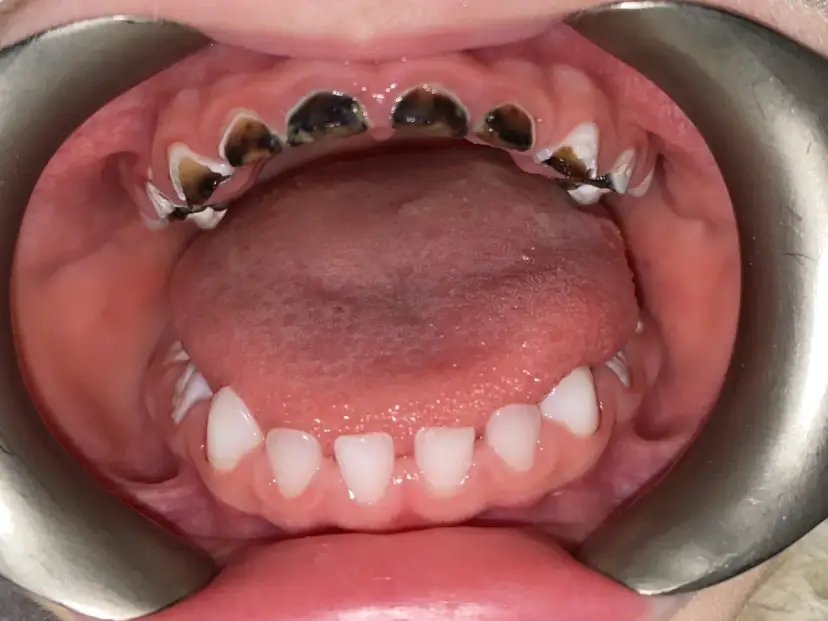

Czy ząb mleczny z próchnicą trzeba usunąć? Poznaj konsekwencje, nowoczesne metody leczenia i wskazania do ekstrakcji. Podejmij świadomą decyzję!